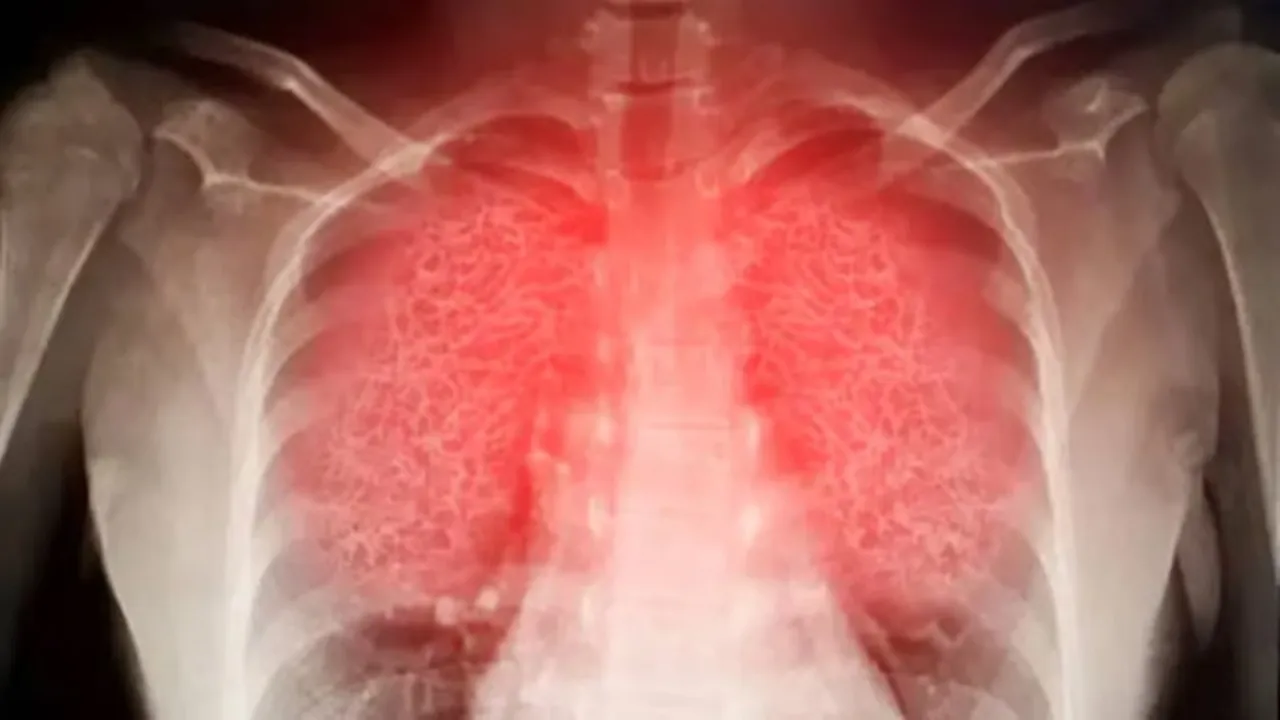

ব্যায়াম সাধারণত ফুসফুসের ক্ষমতা বাড়ায়, হার্টকে শক্তিশালী করে এবং রক্তসঞ্চালন উন্নত করে। কিন্তু যখন বাতাসে নাইট্রোজেন ডাই–অক্সাইড বা ওজোনের মাত্রা বেশি থাকে, তখন ব্যায়ামের সময় দ্রুত শ্বাস নেওয়ার ফলে এসব কণাগুলো সরাসরি ফুসফুসের গভীরে চলে যায়। এতে শ্বাসনালিতে প্রদাহ তৈরি হয় এবং ফুসফুসের স্বাভাবিক কার্যক্ষমতা কমে যায়। এই প্রদাহের কারণে ব্যায়াম করতে গেলে বুক ভারি লাগে, শ্বাস নিতে কষ্ট হয় এবং শরীর দ্রুত ক্লান্ত হয়ে পড়ে। গবেষণায় দেখা যাচ্ছে যে যাঁরা নিয়মিত দূষিত বাতাসে দৌড়ান, তাঁদের ফুসফুসের গ্রোথ কমে যায় এবং দীর্ঘমেয়াদে শ্বাসকষ্টের ঝুঁকি বাড়ে।